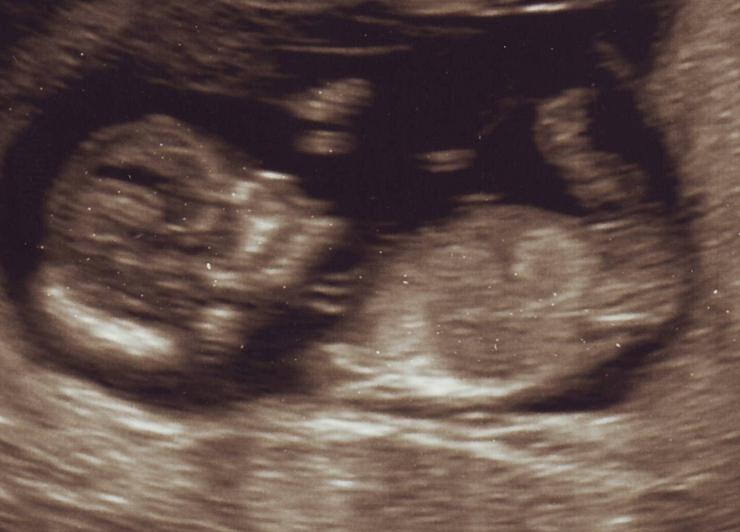

I was 12w5d when these pics were taken. It's taken me 4 weeks to pluck up enough courage to post my pics, so please be truthful but gentle with your guesses! I got my date for my anomaly scan today (18th July) so felt that 3 weeks was plenty of time to nubsess before I find out. Baby was measuring according to my LMP at 12w5d although I swore that I ovulated later, but perhaps not! :think:

Attachment 11945

Attachment 11946